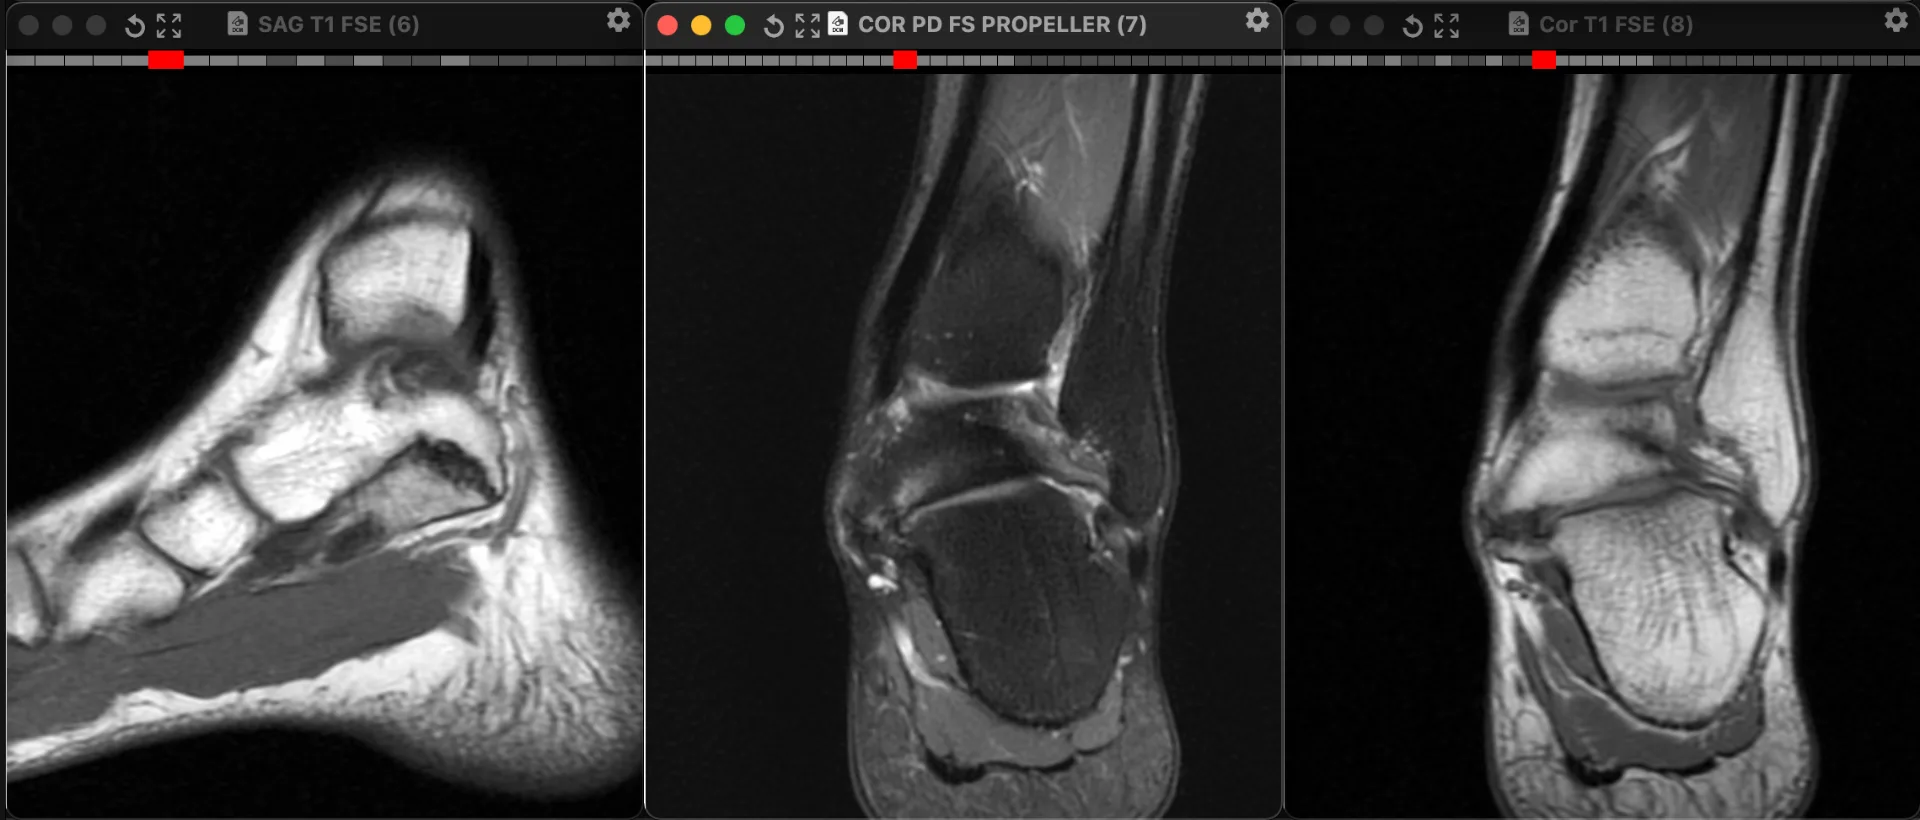

Один из вариантов тарзальной коалиции: таранно-пяточный синдесмоз. Напомню, что тарзальной называется патологическое сочленение между костями плюсны и предплюсны, может быть в виде синостоза, синхондроза и синдесмоза. Если имеется синдесмоз (как здесь), то хроническая его перегрузка приводит к артрозу и всем его типичным проявлениям, как здесь: неровностям контактных поверхностпей, субхондральные отёк и полости (кисты). Локально болит, особенно при нагрузке. Пациент 26 лет.

🔥 43👍 20